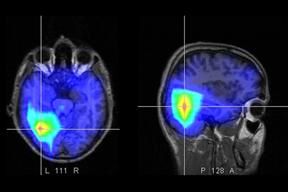

Los factores que aumentan el riesgo de padecer un accidente cerebrovascular (ACV) o stroke difieren en su importancia relativa antes y después de los 45 años. En el primer grupo son señales de alerta el consumo de drogas ilegales, el mal de Chagas y las migrañas con aura.

"El más frecuente es el ACV isquémico, o infarto cerebral, producido por la súbita oclusión de una arteria, y en menor proporción el hemorrágico, ocasionado por la ruptura de una arteria del cerebro", explica el doctor Luciano Sposato, director del Renacer, del Centro de Stroke del Instituto de Neurociencias de la Fundación Favaloro y de la Unidad de Stroke del Instituto de Neurología Cognitiva (Ineco), al tiempo que puntualiza que el análisis de casi 1991 casos permitieron obtener conclusiones sobre las diferencias que muestra el stroke entre jóvenes y no jóvenes.